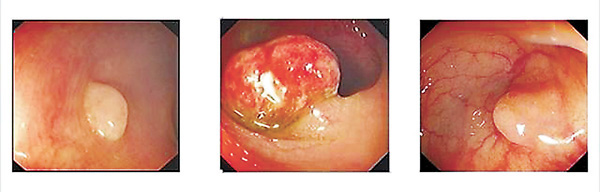

●(左至右)增生性瘜肉、腺瘤性瘜肉和鋸齒狀瘤。

大腸瘜肉是良性上皮腫瘤,由大腸內壁的上皮細胞產生。在傳統上,結腸瘜肉分為三類:增生性瘜肉、腺瘤和瘜肉病綜合症。

一·增生性瘜肉

增生性瘜肉佔所有瘜肉約90%,是一種良性突起,它們的直徑通常小於0.5cm。增生性瘜肉最常見於成年人的乙狀結腸內。以前,增生性瘜肉在臨床上被認為是完全無關緊要,但現在,增生性瘜肉的出現也被認為有轉為惡性腫瘤的可能。如乙狀結腸附近有5個或更多的鋸齒狀瘜肉,其中兩個或多個直徑大於10cm,或瘜肉總數多於20個等,這種瘜肉被認為可能具有轉化腺瘤的可能。

二·腺瘤

腺瘤約佔所有瘜肉的10%。 大多數腺瘤瘜肉(約90%)很小,通常直徑小於1cm,並且惡性可能性很小;而其中一種高風險的腺瘤叫進行性腺瘤,直徑1cm以上,這瘤從病理化驗可得知有絨毛成分及高度細胞異化。另外,瘜肉的形狀或總體結構在臨床上也很重要,有莖的息肉稱為帶蒂,沒有莖的瘜肉稱為無柄。無柄息肉比帶蒂的大瘜肉更危險,因為侵入性細胞從腫瘤遷移到黏膜下結構的途徑更短;而使用內窺鏡把無柄瘜肉切除的難度更高。

三·瘜肉症候群

瘜肉症候群是遺傳性的,此症候群增加了出現瘜肉的風險。瘜肉症候群最常見的種類為遺傳性非瘜肉結直腸癌綜合症。此病患者特別容易患腺瘤性瘜肉及無柄鋸齒狀腺瘤,這兩種病都有轉為癌症的傾向。